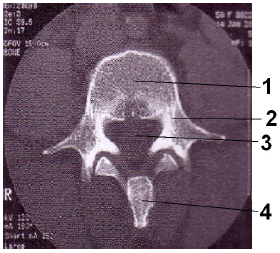

Marque a opção que contém corretamente os respectivos números totais de vértebras humanas dos segmentos cervical, torácico e lombar, exatamente nesta ordem.

Assinale a alternativa que representa, em ordem crescente, as estruturas assinaladas na imagem tomográfica anteriormente apresentada.